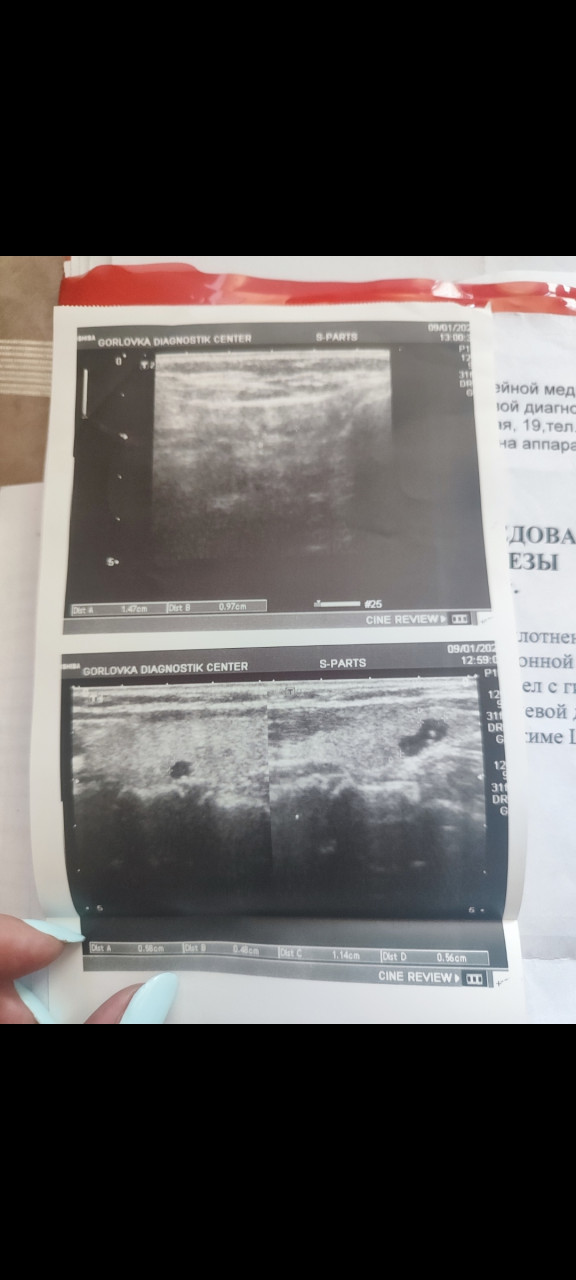

Здравствуйте! Подскажите, пожалуйста, мои дальнейшие действия с такими результатами УЗИ щитовидной железы и анализами? Все ли там в относительной норме? Заранее спасибо!

Здравствуйте. По УЗИ  диффузно-узловой зоб 1 степени, оба узла с признаками доброкачественных (TI-RADS 2), гормоны щитовидной железы (ТТГ и Т4)  в пределах нормы. Пока поводов для тревоги нет и сейчас требуется:

-динамическое наблюдение УЗИ раз в 6-12 месяцев

-контроль ТТГ 1 раз в год

-при росте узлов или появлении жалоб необходимо дообследование (например ТПО, ТГ антитела, пункция при необходимости).

Лимфоузел справа  реактивный вероятно на фоне гастрита или ЛОР-воспаления, но стоит проследить в динамике.